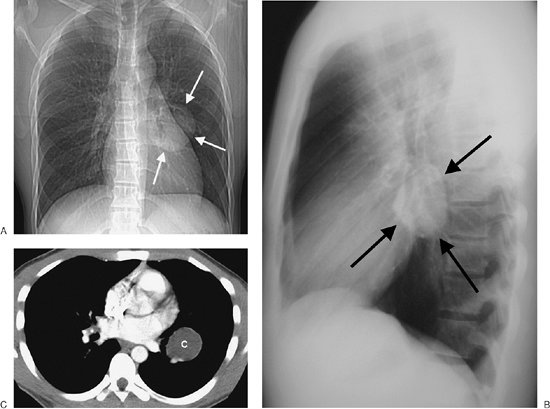

FIGURE 6-10. Benign cystic thymoma. A: PA chest radiograph shows an abnormal left mediastinal contour (arrow). B: Lateral view shows a round, circumscribed mass with a high-attenuation rim in the anterior mediastinum (arrows). C: CT scan shows a mass of soft tissue attenuation (T) with dense rim calcification anterior to the ascending aorta.